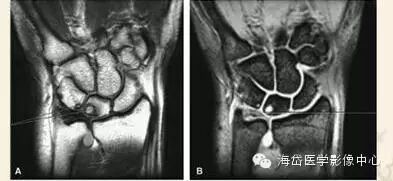

②MRI:MRI对骨髓变化敏感,在骨损伤早期就能反映出骨髓水肿性改变,可做到早期诊断。

随压迫时间延长MRI可见高信号(T2WI)逐渐增强,并形成透镜样改变,晚期形成“双线”或“双环”征。“双环”征提示坏死区内可能有新骨形成,“双线”征表明骨坏死区有瘢痕组织形成。

由于尺骨阴性、阳性变异引起的骨坏死是可逆的,当尺骨变异被纠正后骨坏死可以转化为正常骨结构。因此MRI除可用于早期诊断外还可作为有效的动态观察手段,当骨髓水肿性变化无减轻、消失,反而逐渐明显时,提示临床应早期解除桥联状态(主要是解除压迫),可有效防止月骨、三角骨坏死的发生或降低其发生率。